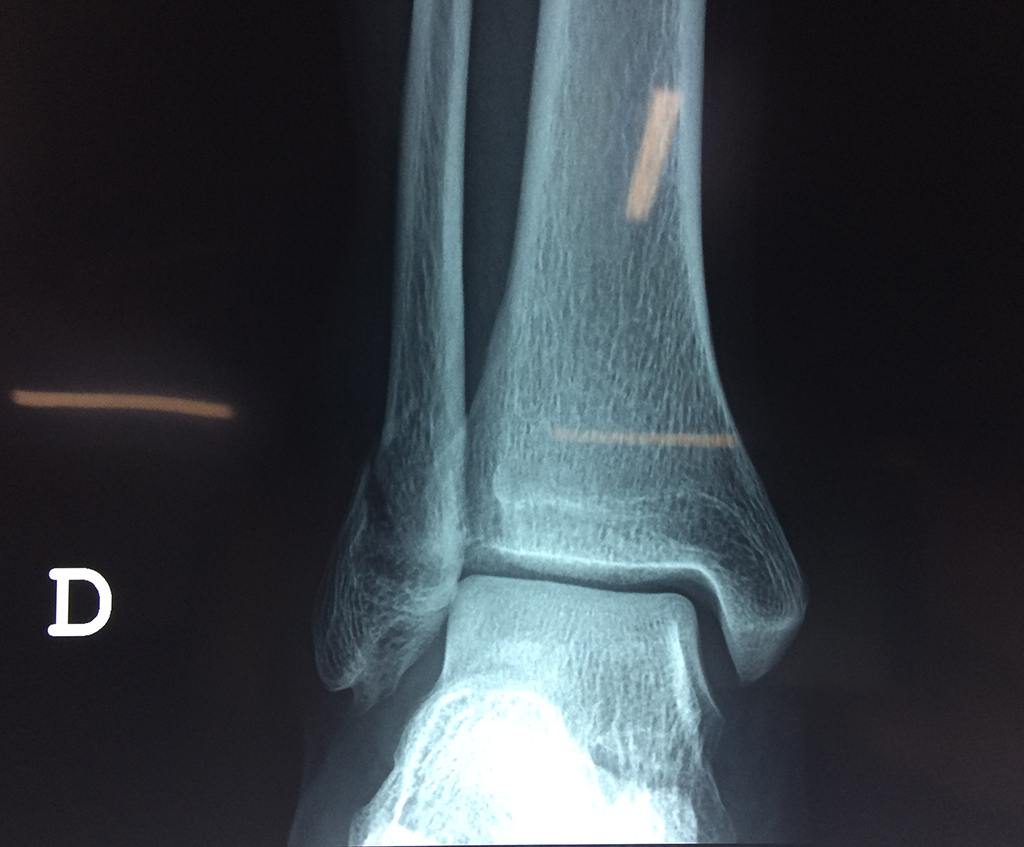

Cuando se necesita cirugía, es probable que esta implique el uso de clavijas de metal, tornillos o placas para sostener los huesos en su lugar mientras la fractura se consolida. Los elementos de soporte pueden ser temporales o permanentes.